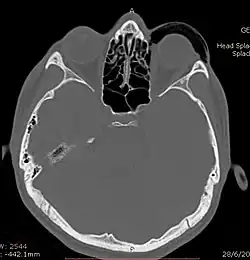

| Woman with preorbital swelling in orbital emphysema shown in CT scans | |

Computed tomography (CT)

Computed tomography is effective and sensitive in the diagnosis of orbital emphysema,[3][37] as it can confirm the anatomical location and size of air, bony defects, indentation of the eyeball, and the condition of the optic nerve, as well as the presence of any extraocular muscle entrapment and herniation of preorbital fat into the sinus cavities.[3][15][38] The location of the orbital emphysema is present near the site of the fracture.[1][3] The scans are usually taken along the transverse plane. Transverse images allow the evaluation of fractures in medial and lateral orbital walls. By reformatting these transverse images or taking coronal images, the examination of orbital floor and roof is permitted. Helical scanning is preferred as it has a lower imaging time and radiation dose comparing to conventional scanning, especially when reforming transverse helical scans into coronal images.[3] The staging of orbital emphysema can then be determined with visual acuity examination and ophthalmoscopy.[6] A disadvantage of using a CT scan is that when detecting air after orbital trauma, the presence of a wooden foreign object can give a false positive result of orbital emphysema. The wooden object can mimic the presence of orbital emphysema. Therefore, patients’ medical history is crucial in making the correct diagnosis.[3]